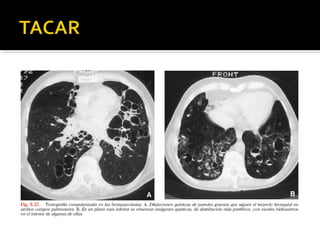

 TACAR: S 96% E 93%

 Signos : falta de ahusamiento bronquial,

engrosamiento de la pared bronquial,

bronquios visibles a menos de 1cm de la

pleura visceral, signo en “anillo de sello” etc,

 TACAR: S96% E 93%  Signos : falta de ahusamiento bronquial, engrosamiento de la pared bronquial, bronquios visibles a menos de 1cm de la pleura visceral, signo en “anillo de sello” etc,